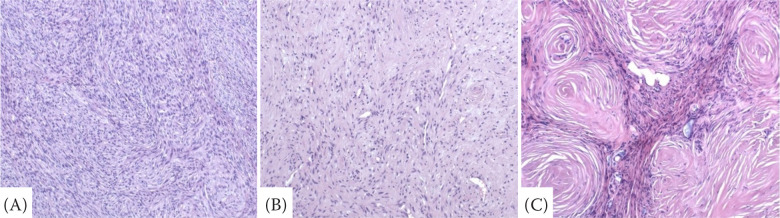

Peripheral nerve sheath tumours (PNSTs) are rare in the mammary glands of dogs. Here, we report a case of a schwannoma, composed of two parts, of the mammary gland of a dog. The first part consists of clusters of uncircumscribed, alternating, more concentrated and looser regions. In the more concentrated parts, typical fascicularly arranged schwannoma intermingle in plexiform arrangement, more subtle in appearance than in neuronal tumour areas. The second part undergoes regression consisting predominantly of residual shorter rosettes of cells with the presence of a peculiar variably sized swirling of target-like formations consisting of compact, thicker, pinkish lamellae also with occasional adjacent cells. Immunohistochemically, the tumour cells are positive for evidence of vimentin and neuro-specific enolase. They exhibit the variable expression of the S-100 protein, show mild CD56 positivity, and focally mildly accentuated proliferative activity as assessed by Ki-67. The tumour elements are negative for evidence of cytokeratin 7, cytokeratin 20, and oestrogen receptors. Hybrid tumours may change their morphology in combination with atypical localisation and may be underdiagnosed in veterinary biopsy practice. They differ from epithelial tumours prognostically, as well as in their development and behaviour, therefore it is essential to clearly differentiate them.